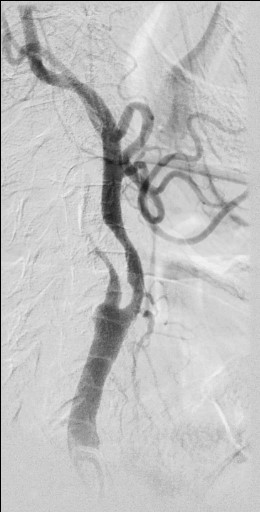

13:00 Больной подан в рентгеноперационную, выполнена церебральная ангиография: Ангиографические признаки атеросклеротического процесса брахиоцефальных артерий, тромботической окклюзии правой ВСА(Рис1), окклюзия левых ВСА(Рис3) и ПА(Рис2).

Рис4 заполнение системы левой ВСА через левую заднюю соединительную артерию.

рис. 1 рис. 2

рис. 3 рис. 4